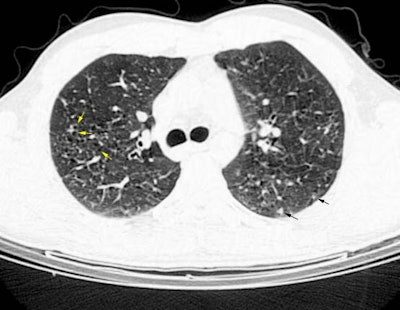

The patient below was a young male smoker who complained of increasing shortness of breath. The HRCT scan revealed scattered small cysts (yellow arrows) and small peripheral nodules (black arrows). Some underlying mosaic parenchymal attenuation is also suggested. Open lung biopsy was performed and the diagnosis was eosinophilic granuloma.